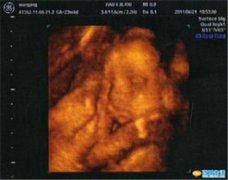

早孕诊断

宫外孕